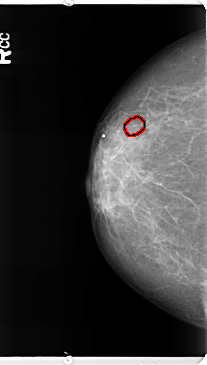

FILE: B_3364_1.RIGHT_MLO.OVERLAY

TOTAL_ABNORMALITIES 1

ABNORMALITY 1

LESION_TYPE CALCIFICATION TYPE PLEOMORPHIC DISTRIBUTION CLUSTERED

ASSESSMENT 4

SUBTLETY 3

PATHOLOGY BENIGN

TOTAL_OUTLINES 1

BOUNDARY